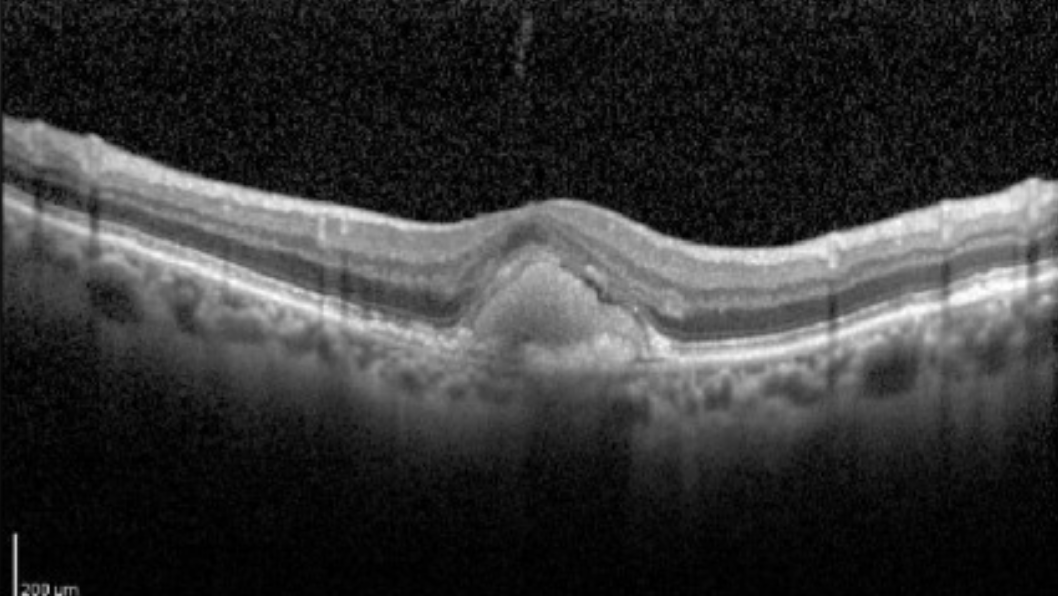

Rocha Bastos R, Ferreira CS, Brandão E, Falcão-Reis F, Carneiro ÂM. Multimodal Image Analysis in Acquired Vitelliform Lesions and Adult-Onset Foveomacular Vitelliform Dystrophy. J Ophthalmol. 2016;2016:6037537. doi:10.1155/2016/6037537 (image cropped)

OCT macula to rule out macular involvement

Genetic testing: BEST1 mutation

Arden Ratio: 1.50

• Adult Foveomacular Vitelliform Retinal Dystrophy, OU